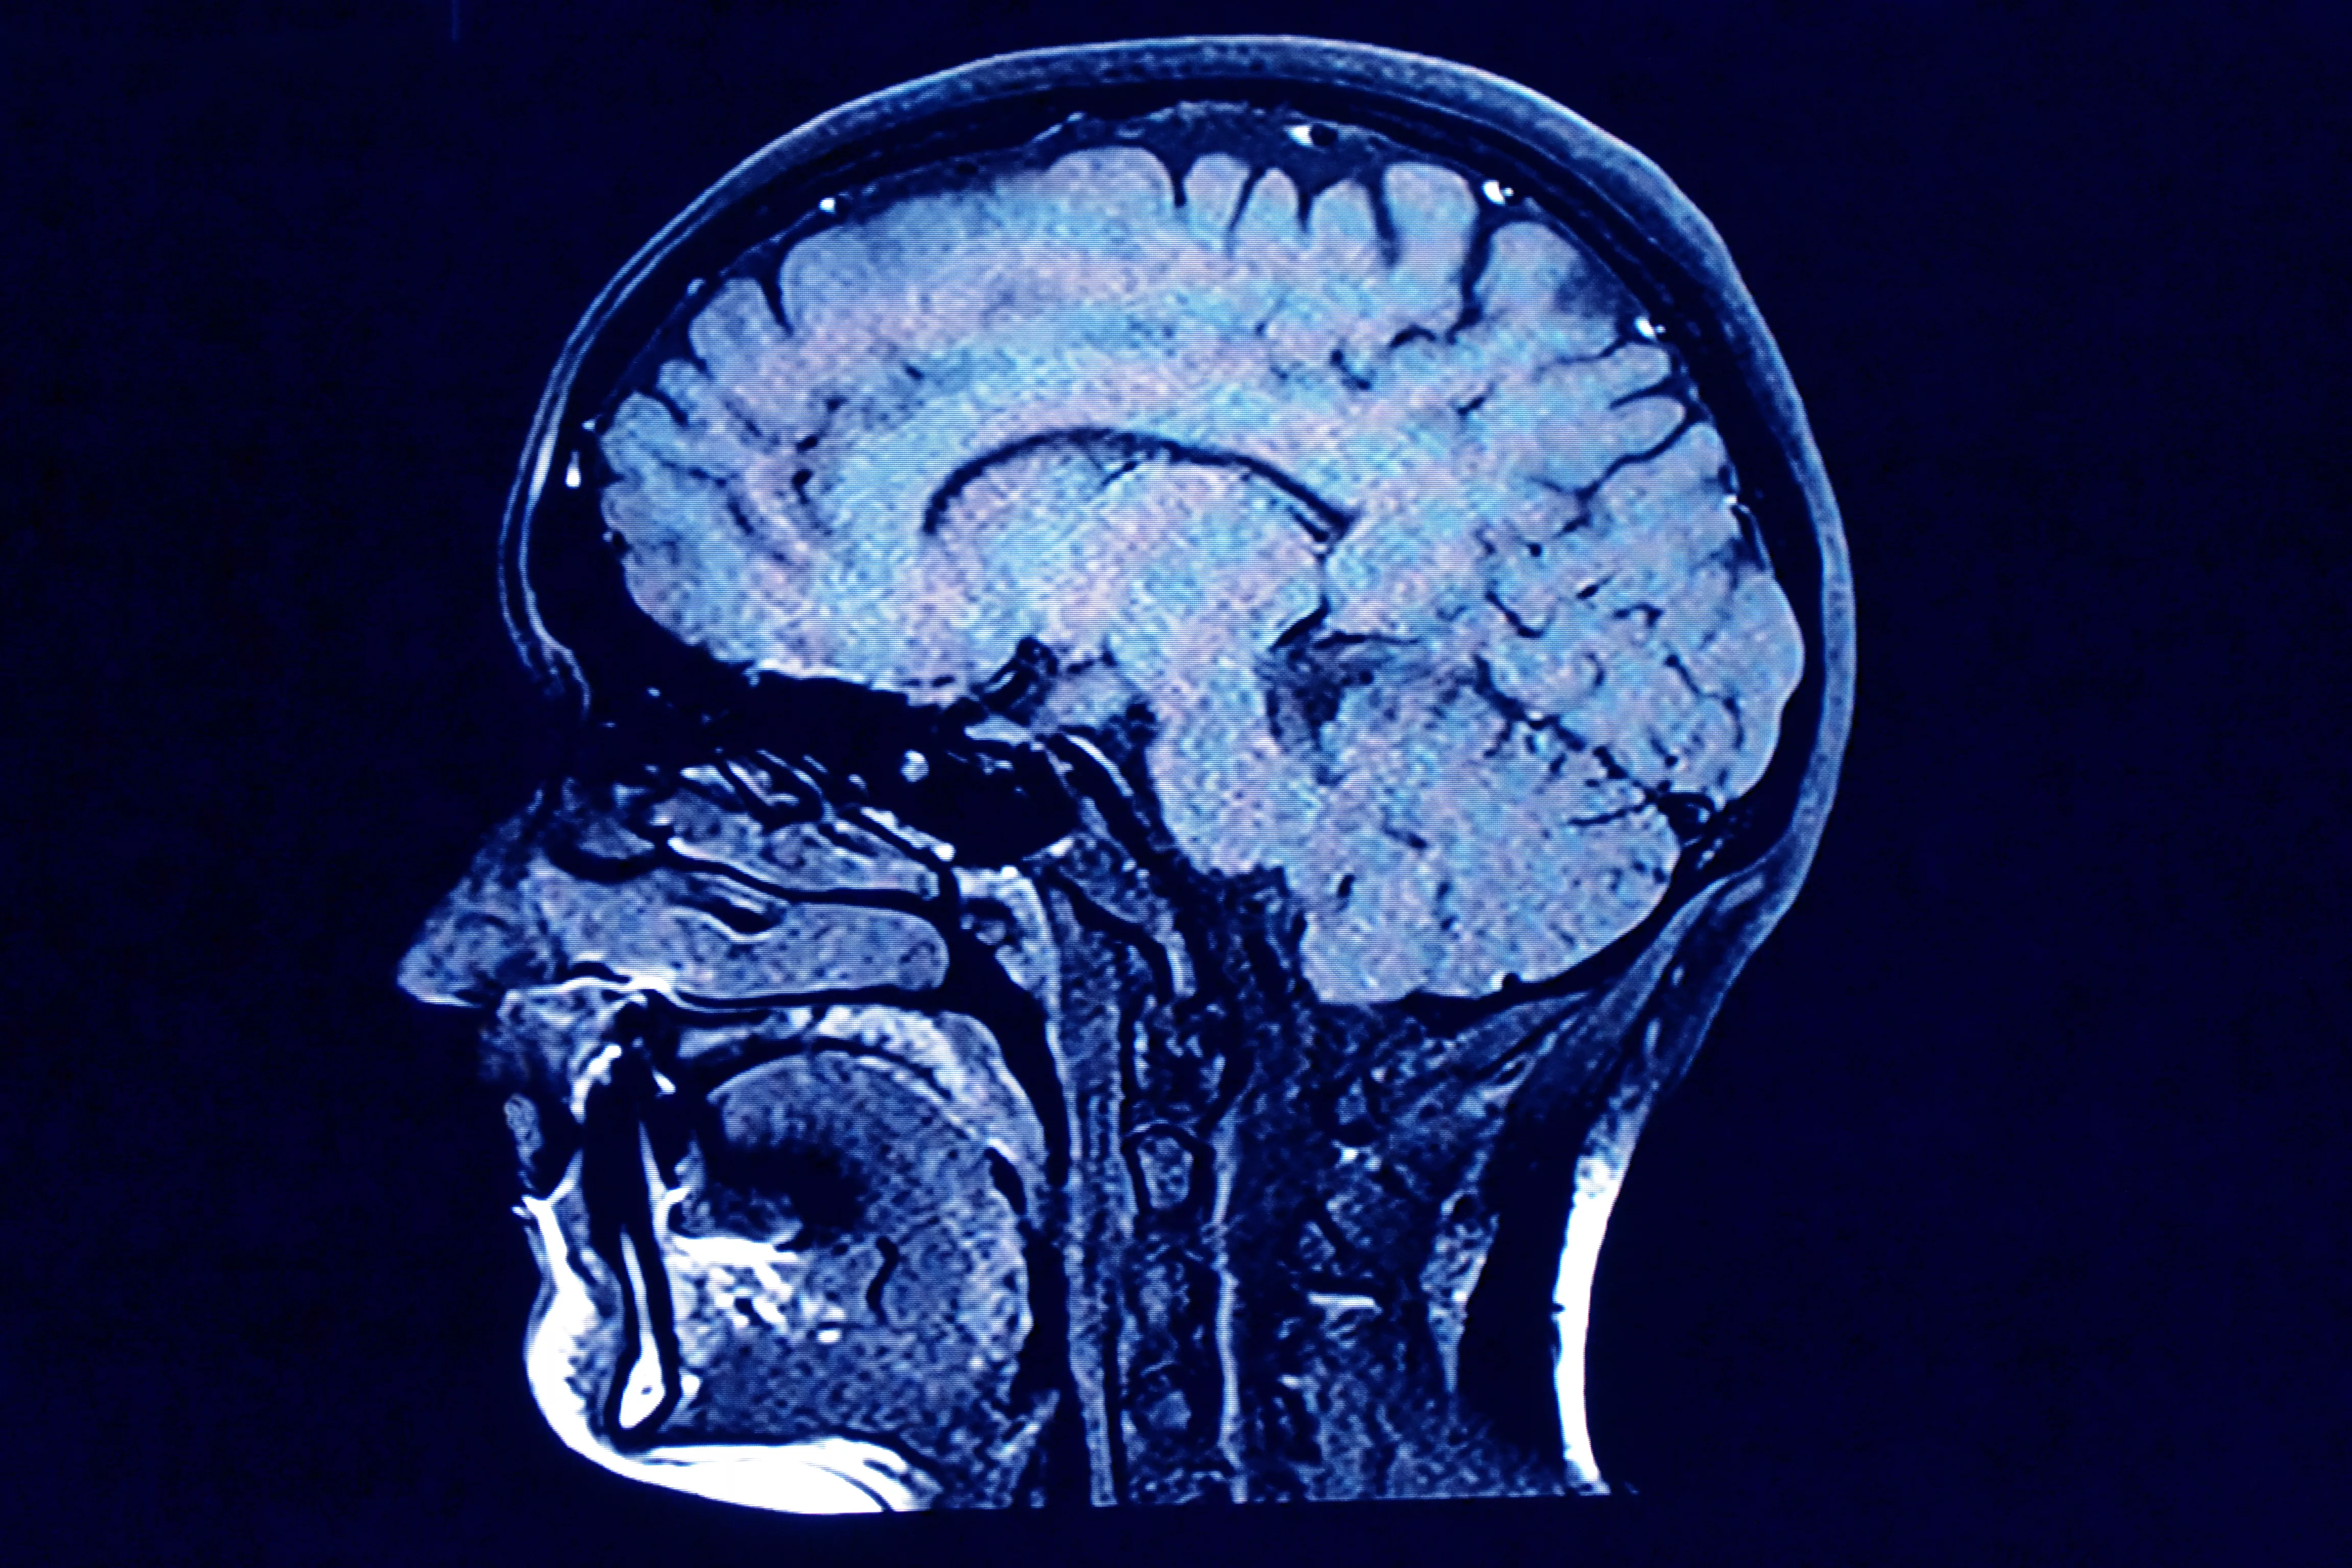

More under this adMore under this adThe family was shocked when they were presented with the MRI of her brain. Amanda said:

There was atrophy of the brain - it was basically wasting away. She was like an old dementia patient with lots of blank spaces in her brain.